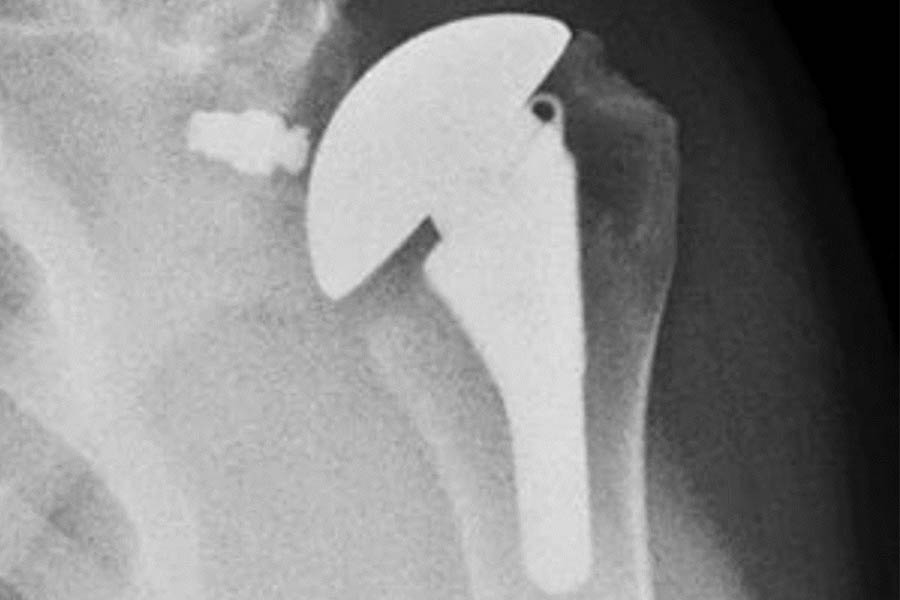

Breakthrough Shoulder Prosthesis Promises Improved Outcomes

Shoulder arthroplasty is ordinarily done either as anatomic shoulder replacement or reverse total shoulder replacement, distinctly different approaches that can limit the placement of prostheses if a revision surgery is later required. William N. Levine, Chair of the Department of Orthopedic Surgery at NewYork-Presbyterian/Columbia, was a member of a team of surgeons that helped develop a transformational shoulder prosthesis that can be used for either surgical approach and allows conversion of a failed anatomic replacement. The groundbreaking prosthesis is expected to markedly improve patient outcomes.

Left: Pre-operative image of shoulder before total shoulder arthroplasty. Right: Post-operative image showing the new prosthesis in place.